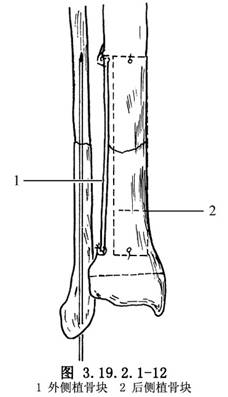

11.4 4.植骨

在脛骨遠、近端的外側和後側,用骨刀鑿一薄層皮質,上端達骨近側斷端上5~7.5cm,下端儘可能接近脛骨遠端骨骺板,但不能損傷它。從對側脛骨切取相應大小的骨膜骨瓣兩塊,骨瓣上下端鑽孔,貼附於已準備好的脛骨外側和後側的粗糙面上,以不吸收線縫合固定於脛骨遠、近端(圖3.19.2.1-12)。植骨骨瓣間和假關節處植入松質骨碎骨塊和皮質骨細骨條(圖3.19.2.1-13)。